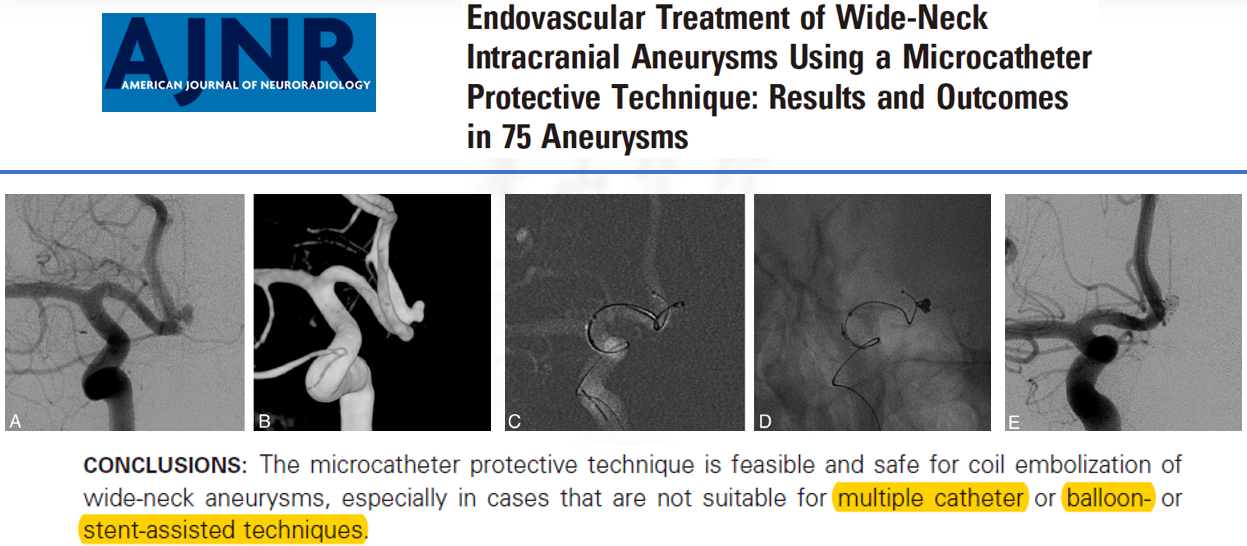

11. 回头看看,我们在这个案例中要注意哪些细节。首先就是对整个病例的治疗策略:动脉瘤合并狭窄的案例其实在后循环病变中更多,AJNR的这篇文章认为在这样的病例中使用支架并不额外增加卒中事件的发生率。但我们在临床工作中需要权衡利弊,对于狭窄节段,先扩还是后扩;对于支架类型,开环和闭环如何选择?相信每个人有自己的考量,针对不同的病例特点,选择最合适的治疗方法。此外,动脉瘤填塞策略、微导管(微导丝)保护技术的应用,也会使动脉瘤的治疗效果锦上添花。